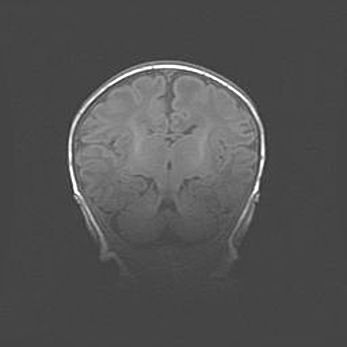

Открытая гидроцефалия.

Возраст: 6 месяцев 15 дней

Вес: 6200 г

Пол: женский

Окружность головы: 41 см

Срок гестации: 38 недель

Гидроцефалия головного мозга у новорожденных – это скопление избыточного количества цереброспинальной жидкости в головном мозге. Ее избыточное скопление в мозге приводит к патологическому расширению желудочков мозга (четырех полостей, расположенных в глубине белого вещества мозга, заполненных цереброспинальной жидкостью и связанных узкими проходами).

Открытый тип гидроцефалии (сообщающаяся) наблюдается тогда, когда нарушен механизм всасывания ликвора в системный кровоток. При этом типе причиной заболевания чаще всего является перенесенные ранее инфекции (например: менингит),  либо же наличие крови в субарахноидальном пространстве.